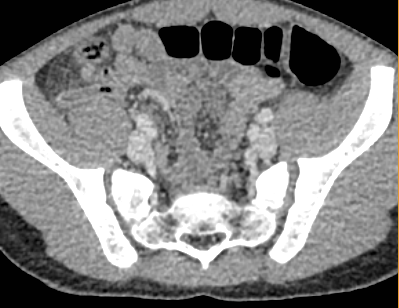

Because of gas obscuring the appendix on ultrasound, a CT is required to assess this case. A CT with contrast is preferred where possible. It will help with assessment of an inflamed appendix.

Pertinent Imaging Observations

Click on the links below to view images from the study, and assess these key findings as best you can.

What is your Diagnosis now that you have seen the imaging results?

Acute uncomplicated appendicitis. (No evidence of perforation or abscess)